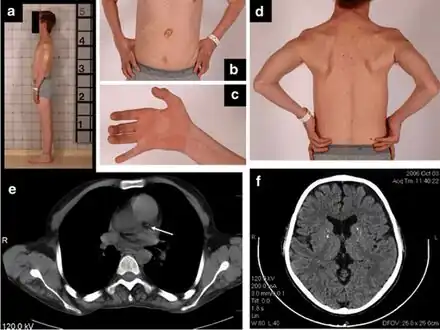

a) Thin habitus b)gastrostomy tube c) clawed hand d) muscle wasting upper trunk e)calcification left coronary artery f) atrophy and calcifications of the basal ganglia

a) Thin habitus b)gastrostomy tube c) clawed hand d) muscle wasting upper trunk e)calcification left coronary artery f) atrophy and calcifications of the basal ganglia Rickets in cystinosis. a- A cystinosis child with evident rachitic bone deformities. b- Active rachitic bone disease in X-Rays